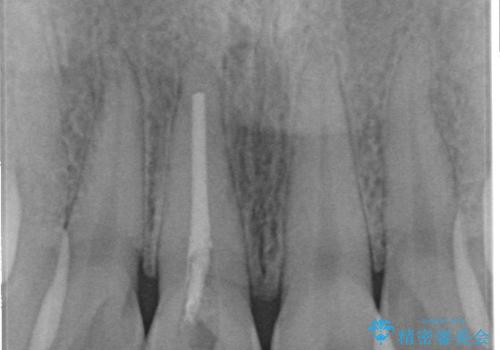

根管治療は歯内の治療なので患者様には見えない場所ですが、ここが細菌で汚染されると激しい痛みや長引く違和感の原因になります。

当院では、清潔な治療を徹底し、顕微鏡を使用した精密な治療を行っています。

症状や根管の状態により、治療金額が異なります(5~10万円目安)。治療回数による費用負担の増減はありません。